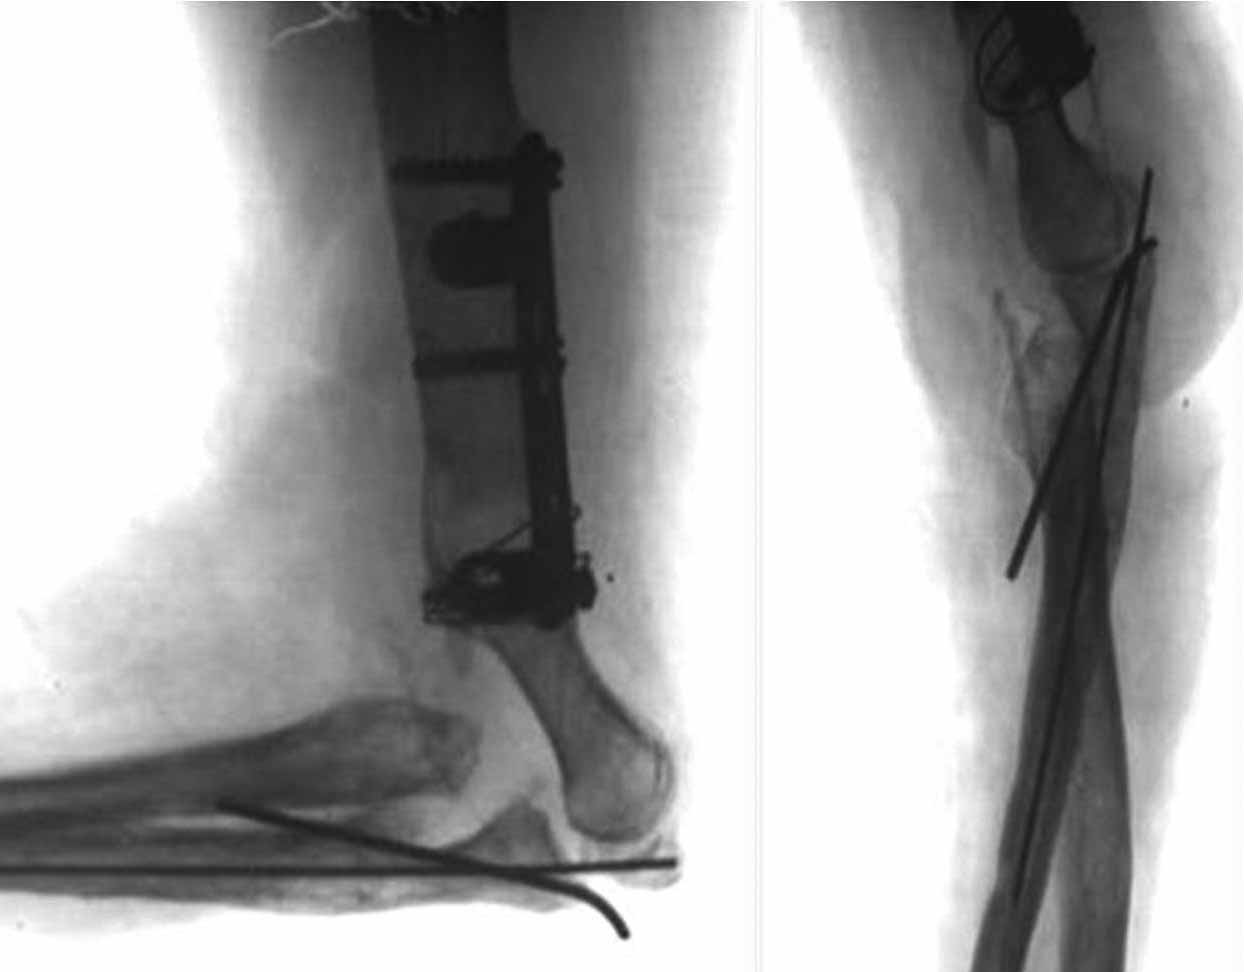

Снимки в проекции "как получилось". Попозже сам уложу на столе правильно.

Оперировали в четверг. Начали с лучевой кости. Легко фиксировали её TEN закрыто ретроградно. Приняли решение ревизовать сустав задним доступом. Открытии локтевую кость , выполнен остеосинтез ульнарным блокируемым гвоздём. Продолжили разрез на плечо. Отломки мыщелков смещены во всех мыслимых направлениях, ротированы, практически лишены связи с мягкими тканями и окружены хрящевой мозолью. Имеются фиброзные сращения отломков плеча с проксимальными отделами костей предплечья. Проксимальный фрагмент плеча упирается в суставные поверхности предплечья. Осумкованные остатки одежды. Операционная картина смещения отломков не позволяла сделать «приблизительную репозицию» - для минимального сближения отломков их было необходимо полностью мобилизовать. Мыщелковые отломки собраны в единый блок, фиксированы спицами и финтами. Сухожилие трицепса сохранило связь с локтевым отростком по наружной поверхности. Локтевой нерв из заднего доступа выявить не удалось. Внутренний надмыщелок - где то сильно спереди. Топографически по краю локтевой кости удалось обнаружить атрофичный тяж, напоминающий раздавленный нерв. С ревизией не упорствовали – повреждение нерва должно быть очень протяжённым и слишком выражен рубцовый процесс с этой зоне. В дальнейшем надо, видимо, будет делать «вставку». После собирания мыщелков состыковали полученный конгломерат с проксимальной частью плеча. Фиксация реконструктивной LCP за наружный, самый крупный фрагмент в районе головки мыщелка. В дефект метафиза – гранулированный ‘’CronOS’’ + ванкомицин. После тщательных санаций и лаважей перешли к закрыванию раны, намереваясь смонтировать Илизарова. Немедленно выяснилось, что как раз на самой середине раны, над локтевым отростком края кожи сводятся с критическим натяжением. Кости предплечья при малейшем движении в суставе вывихивались кнаружи, что потребовало фиксации спицей сустава (луч-головка). Разгибание в суставе также не давало возможности ушить кожу без натяжения. Причиной помехи виделось изменение взаимоотношений тканей и рубцовый конгломерат по передней поверхности плеча и локтевого сустава, после репозиции отломков сместившийся кпереди. Операционный отёк был минимален. Сразу родилось запоздалое соображение. Было бы не лишним перед открытым вмешательством наложить дистракционный аппарат, дать дозированное удлинение за предплечье и создать запас пространства, выполняя некоторый «таксис» отломков плеча, а не идти сразу на прямую репозицию. Почему то задним умом думается, что это значительно бы облегчило работу с мягкими тканями. Рана была закрыта с натяжением краёв при помощи эластичных нитей на степлерных скобках. В таких условиях пришлось отказаться от монтажа илизаровского АВФ и активизации сустава – теперь рану надо закрывать этапно. Смонтирован ExFIX c шарниром по осевой спице – сама спица удалена. Наложен VAC на рану. Оставили катетер в сплетении, обезболивали 3 суток маркаином.

Ну и ещё, а после операции можно сделать рентген так, чтобы самим было понятно, где кости, а где металл? Как минимум, некорректно!